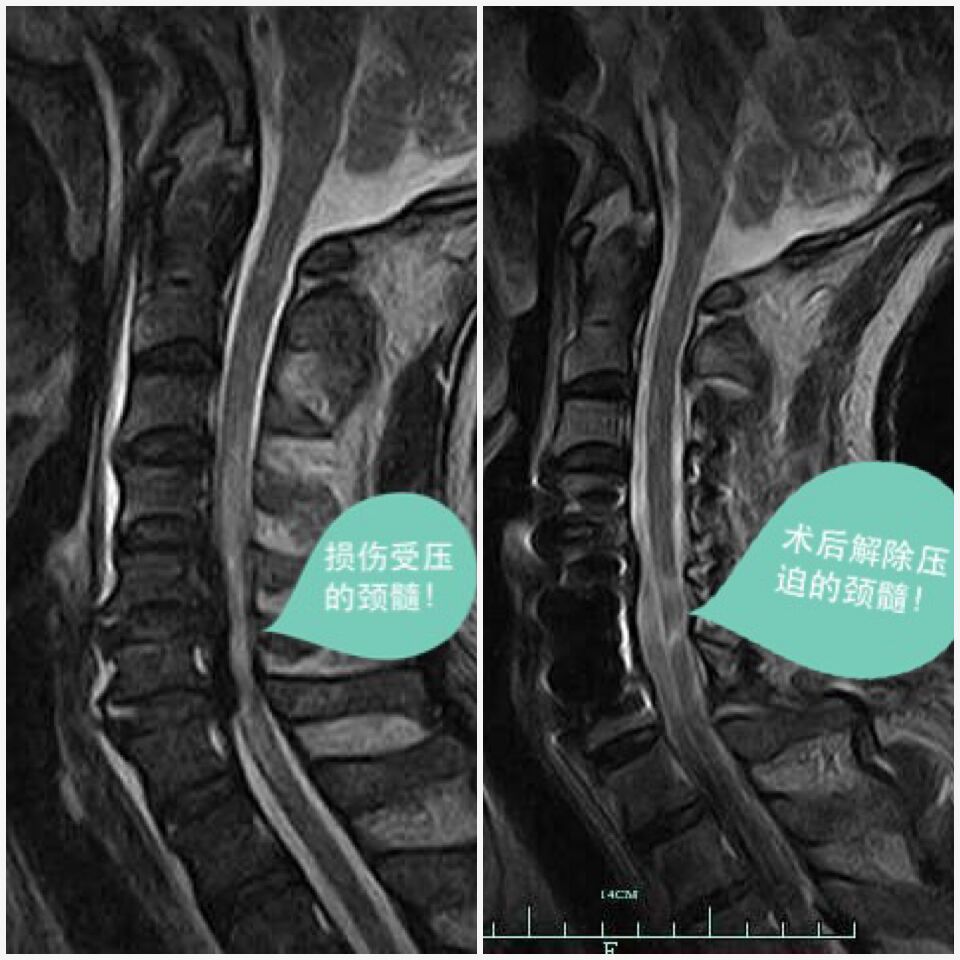

本网讯(何鑫东/文/图)几月前,新昌县人民医院脊柱外科成功为一位车祸致严重颈椎颈髓损伤伴四肢瘫痪的病人施行了颈椎前、后联合手术。治疗前病人瘫痪在床,四肢行无法活动,各种感觉几乎丧失,经手术治疗并经积极康复锻炼后,病人已能再次下地活动,目前已出院。

63日,病人因车祸收住脊柱外科病房,当时病人神智尚清,但心率血压不稳定,处于休克状态,病情危重。时间就是一切,接诊的医护人员立即予升压、扩容、抗休克等积极生命支持治疗,使病人的休克状态在短期内得到控制、改善。等病人血压稳定后通过颈椎X线、CTMRI(磁共振)等检查后诊断为颈椎过伸性损伤,颈髓损伤伴四肢瘫、颈后纵韧带骨化、颈椎管狭窄。颈部损伤较为复杂严重,在原先颈椎退变导致椎管狭窄的基础上,突然受到外伤暴力冲击,导致颈椎损伤,并引起严重脊髓损伤,同时因颈髓压迫严重,导致治疗难度加大。根据有关数据统计,此类损伤伤亡及致残率非常高。

近年来新昌县人民医院脊柱外科已成功治疗几十例此类严重颈椎颈髓损伤病人,积累了较为丰富的诊疗经验。脊柱外科董永强主任在听取病情汇报后,认为:患者外伤后严重颈椎、颈髓损伤,目前最需迫切解决的是患者颈椎管狭窄致颈髓受压问题,从颈后方作椎管扩大减压,尽早解除受损颈髓压迫,给予脊髓相当宽裕的空间,让尚未完全死去的受损颈髓有机会恢复过来至关重要,只有尽力让瘫痪的四肢活动起来,才是病人真正需要的效果。同时病人又存在颈椎前方损伤,出现颈椎前方结构不稳定,也需作颈椎前方的稳定手术,但综合考虑病人一般情况欠好,一次性做前、后路的手术创伤大,病人所承受的风险也大,甚至可能会影响整体治疗效果。所以决定分期行颈后、前路手术,先行颈后路充分扩大椎管解除颈髓受压,再择期行颈椎前方稳定手术。

67日9时,董永强手术团队在病人生命体征尚稳定后,在全麻下对病人行第一次颈椎后路减压手术,术中采用目前国际上先进的单开门椎管扩大成形Arch钛板固定术,手术将后方椎管作类似开门样扩大后,颈髓受压基本解除,手术历时2小时,在麻醉清醒后,病人就能感觉到肢体冷暖痛,四肢也有了一些活动,颈后路第一次减压手术取得成功。

手术后一周,病人的四肢瘫症状进一步好转,血压、心率、呼吸等生命体征已较为平稳,董永强手术团队再次为其施行了颈前路手术,本次手术的重点是去除椎管前方骨化韧带、椎间盘等致压物,并做前方稳定融合固定,使颈髓在椎管前后均无受压,完全通畅,并稳定受损颈椎,恢复颈椎的承重、活动的功能。第二次手术后,病人的活动及感觉功能还在神奇的好转,就像一颗差点被折断的嫩苗又重新恢复了生机,顽强的生长起来。